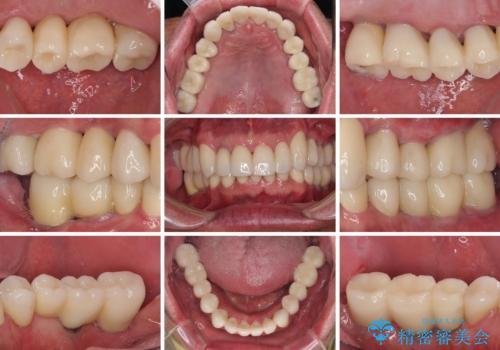

上顎前歯に歯周ポケットの深い部分がありましたが、インプラントの仮歯で奥歯がしっかりと噛めるようになると、1年程度で深い歯周ポケットは解消されました。

前歯部の審美面も大幅に改善され、大変満足していただけました。